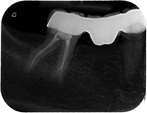

Beispiel eines wurzelkanalbehandelten Zahnes